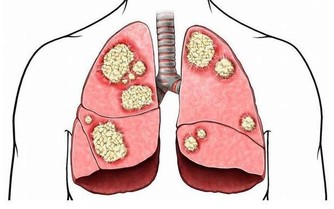

肝臟有不少“天敵”,首推肝炎病毒。換言之,肝炎病毒乃是肝臟健康的首要敵人,它們常將罹患者拖入肝炎——肝硬化——肝癌的死亡之路。目前科學家已發現甲、乙、丙、丁、戊、庚等6種型號肝炎病毒,其中尤以乙、丙、庚等型號最為凶險。最有效的手段是接種疫苗,如甲型、乙型肝炎疫苗。以甲型肝炎為例,疫苗應用近十年,受益者接近1億人,致使該型肝炎的感染率以每年平均22%的速度下降,估計20年後可消滅此病。